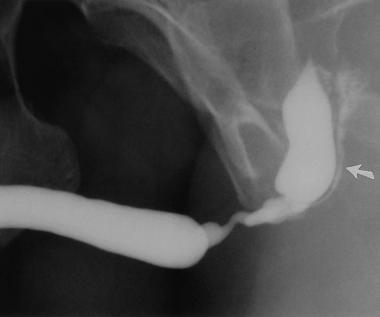

Notice: Trying to access array offset on value of type null in /home/u9176434/en.uretradarligi.com/wp-content/plugins/js_composer/include/autoload/vc-shortcode-autoloader.php on line 64 Notice: Trying to access array offset on value of type null in /home/u9176434/en.uretradarligi.com/wp-content/plugins/js_composer/include/autoload/vc-shortcode-autoloader.php on line 64 The Treatment of Urethral Stricture The treatment of urethral stricture does not involve medications. It involves three surgical methods, which include dilation, endoscopic…